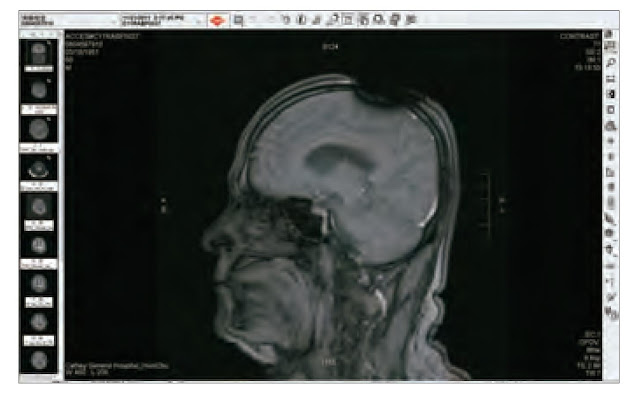

(7) 為什麼不照相或錄影 ??? 再想想, 金剛換體禪並不是開"心", 而是開"頂". 頭頂有沒有打開, 這些法師法王都是光頭或小平頭, 讓人瞧一眼就知道了, 用手機照張相片或錄影就知道了, 何必大費周章, 一群華藏寺法師法王都跑到醫院去照昂貴的MRI呢 ?! 直接證據不用, 卻要用可容造假的間接證據.

(9)"老闆娘, 我也要來一張!"在台灣的健保, 病況需要時每半年可以免費照一張MRI. 所以只要在頭頂上噴灑一些金屬粉末, 並用髮膠固定. 細小的黑粉末是一定可以讓現場醫事檢驗人員既看不出來也摸不出來, 如此就可瞞過醫院. 去看醫生時就說頭內部很不舒服. 要求要照MRI. 公立醫院通常比較不會輕易讓病人照MRI. 少數私立醫院因為購買MRI機器的成本非常昂貴, 因此比較可能會照MRI, 目的顯然是為了回本.

就這樣, 你幾乎不花一毛錢, 就可以輕易瞞天過海又免費照出並拿到"開頂成聖"的MRI影像圖了. 先讓台灣健保替你付費. 如果你要, 還可在公車火車坦克車上打廣告, 再讓台灣信徒把你當大聖德大法王敬拜供養.